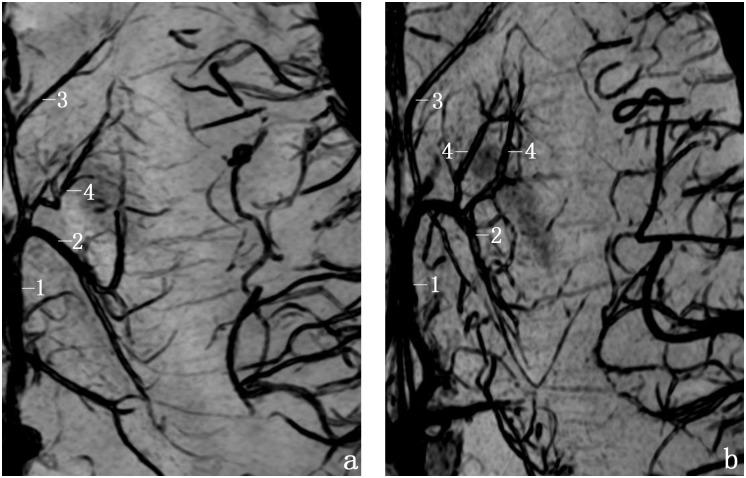

We acquired SWI images in 40 volunteers on a 3.0T MR system using an 8-channel high-resolution phased array coil. The frequencies of the TSV and its tributaries were evaluated. We classified TSV into types I (forming a venous angle) and II (forming a false venous angle). We classified anterior caudate vein (ACV)into types 1 (1 trunk) and 2 (2 trunks) as well as into types A (joiningTSV), B (joining anterior septal vein), and C (joining the angle of both veins).

The TSV drains the areas of caudate nucleus, internal capsule,lentiform nucleus, external capsule, claustrum, extreme capsule and the white matter of the frontoparietal lobes,except thalamus. The frequencies of the TSV, ACV and transverse caudate vein (ACV) were 92.5%, 87.5% and 63.8%, respectively. We found TSV types I and II in 79.7%, and 20.3% with significantly different constitution ratios (P< 0.05). The most common types of ACV were type 1 (90.0%) and type A (64.3%).